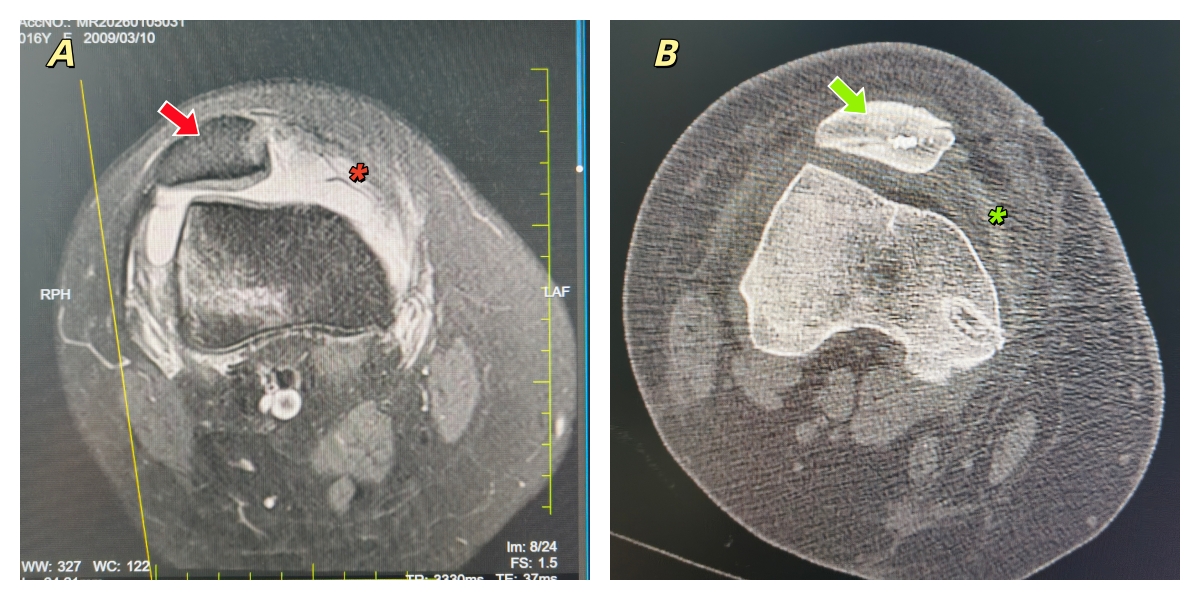

A. MR箭头示半脱位的髌骨,*示撕裂的内侧髌股韧带;B. CT箭头示术后复位的髌骨,*示重建的内侧髌股韧带

患者廖某,16岁女性,因不慎扭伤导致右膝肿痛、功能障碍1天来龙山县人民医院就诊。王梓力医师体查发现右膝肿胀、右髌骨内侧压痛、髌骨恐惧试验(+)。X线示:右膝稍肿胀。王梓力医师仔细询问病史发现患者既往有多次右膝髌骨脱位病史,考虑可能是复发性髌骨脱位。进一步完善MR示右膝髌骨半脱位,右髌骨内侧撕脱骨折,内侧髌股韧带撕裂,股骨外侧髁软骨及软骨下骨挫伤。CT示双下肢无明显力线异常。完善术前准备后,在田宏建、谢龙、包伦明三位医师及麻醉护士团队的紧密配合下,王梓力医师关节镜检查右膝髌骨向外半脱位,无游离体。C臂精准定位股骨内侧髌股韧带等长止点,取患者自体半腱肌进行内侧髌股韧带重建固定。镜检显示髌骨已良好复位、髌骨运动轨迹良好。手术约1小时顺利完成。患者目前恢复良好,已顺利出院。